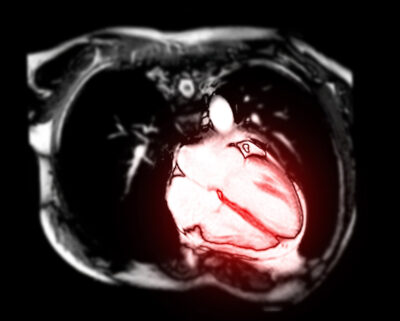

SYNOPSIS: An international study of patients with moderate or asymptomatic severe aortic stenosis has demonstrated that increased amounts of left ventricular fibrosis, as measured by cardiac magnetic resonance imaging, is associated with worse outcomes.

Patients with moderate aortic stenosis (AS) or asymptomatic severe AS are at higher risk of adverse events compared to those with milder degrees of AS. However, unless left ventricular (LV) dysfunction is detected, these patients are not recommended for intervention by current guidelines. Favorable long-term results of transcatheter aortic valve replacement (TAVR) have stimulated interest in identifying parameters in these patients that might help identify those who could benefit from TAVR. Increasing myocardial fibrosis is known to be associated with the progression of LV hypertrophy to LV failure. Thus, this international study of cardiac magnetic resonance (CMR) imaging for the detection of fibrosis in such patients is of interest.

The investigators hypothesized that diffuse interstitial fibrosis as detected by the relative extracellular volume fraction of the LV (ECV%) and the indexed absolute extracellular volume (iECV) or the amount of LV scar tissue represented by late gadolinium enhancement (%LGE) excluding subendocardial infarct related scar would identify those at increased risk of adverse events.